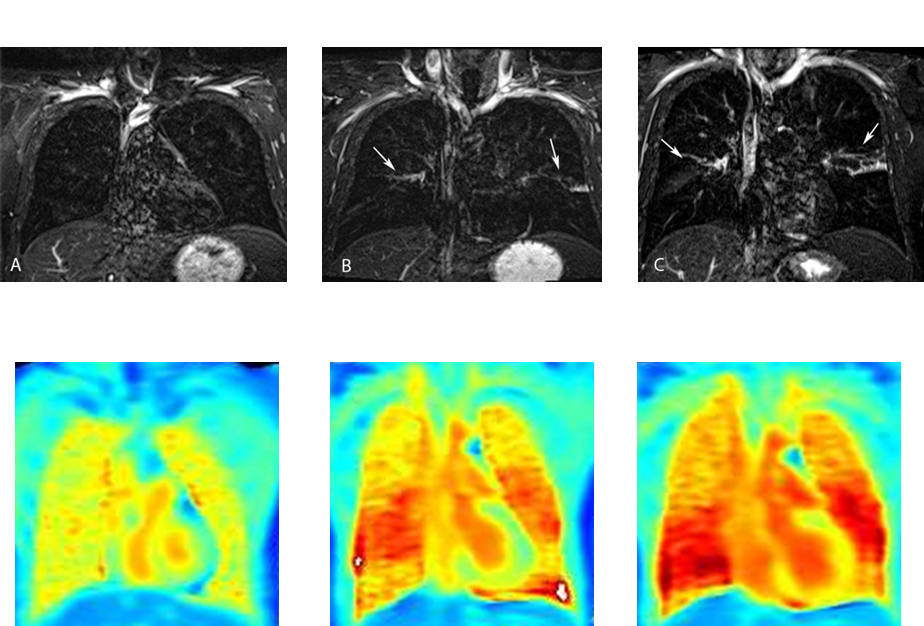

Imaging of local inflammation severity by means of a turbo-inversion recovery magnitude (TIRM) sequence (upper panel) and by oxygen-enhanced T1-mapping (lower panel) in a patient with bronchial asthma prior to (A, left images), 6 hours after (B, middle images) and 24 hours after segmental allergen challenge (C, right images).

We were able to demonstrate that allergen challenge of patients with bronchial asthma induces airway inflammation that can also be visualized by MRI technology. Patients with mild bronchial asthma were challenged by local instillation of allergen during bronchoscopy, a method referred to as segmental allergen challenge, inducing a local inflammatory response in the lung. Repeated MRI scans were then performed using different sequences, and the degree of the inflammation was evaluated both by image analysis and in the traditional way by inflammatory cell count in lung lavage fluid. The results showed excellent agreement between the severity of the inflammation as determined by image analysis and the degree of the inflammation derived from the inflammatory cell count [1, 2].